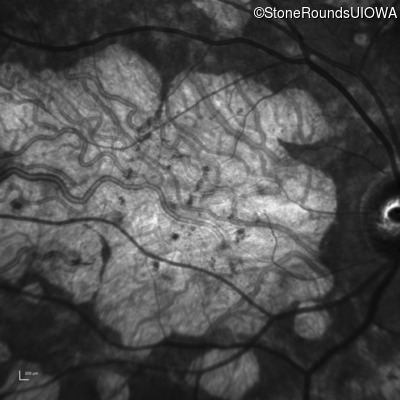

| Age at visit: 54 years |

| AR Stargardt Disease | ABCA4 | Cys205Phe TGC>TTC | Gly863Ala (G)GA>(G)CA | AR |